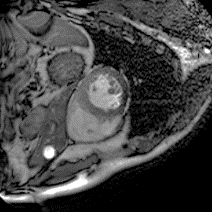

Although supervised deep-learning has achieved promising performance in medical image segmentation, many methods cannot generalize well on unseen data, limiting their real-world applicability. To address this problem, we propose a deep learning-based Bayesian framework, which jointly models image and label statistics, utilizing the domain-irrelevant contour of a medical image for segmentation. Specifically, we first decompose an image into components of contour and basis. Then, we model the expected label as a variable only related to the contour. Finally, we develop a variational Bayesian framework to infer the posterior distributions of these variables, including the contour, the basis, and the label. The framework is implemented with neural networks, thus is referred to as deep Bayesian segmentation. Results on the task of cross-sequence cardiac MRI segmentation show that our method set a new state of the art for model generalizability. Particularly, the BayeSeg model trained with LGE MRI generalized well on T2 images and outperformed other models with great margins, i.e., over 0.47 in terms of average Dice. Our code is available at https://zmiclab.github.io/projects.html.